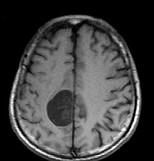

问题 男,68岁,头痛头昏、左侧肢体肌力减退3个月余,请根据所提供图像,选择最可能的诊断()

选项 A.(右顶叶镰旁)恶性脑膜瘤 B.(右顶叶镰旁)胶质瘤 C.(右顶叶镰旁)血管外皮瘤 D.(右顶叶镰旁)脑膜瘤(血管瘤型) E.(右顶叶镰旁)转移瘤

答案 D